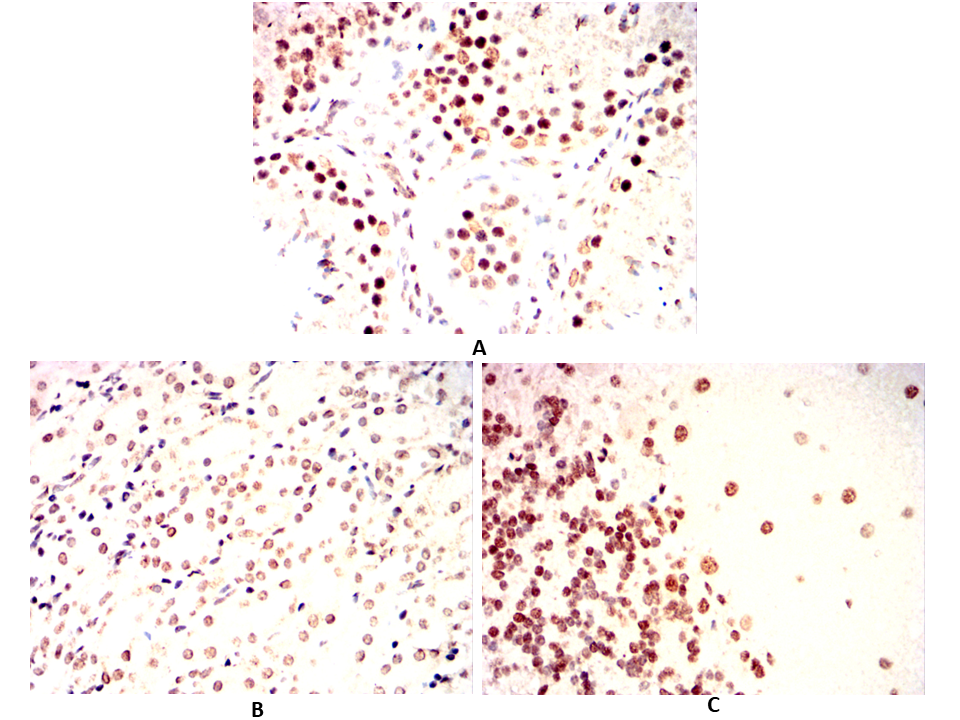

Immunohistochemical analysis of paraffin-embedded Rabbit testicles(A)Rabbit cerebellum(B)Rabbit kidney(C) using ESR1 mouse mAb with DAB staining.